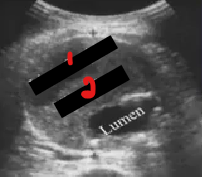

Label the structures crossed out on this image.

What pathology is this?

True lumen

False lumen

Dissecting aneurysm